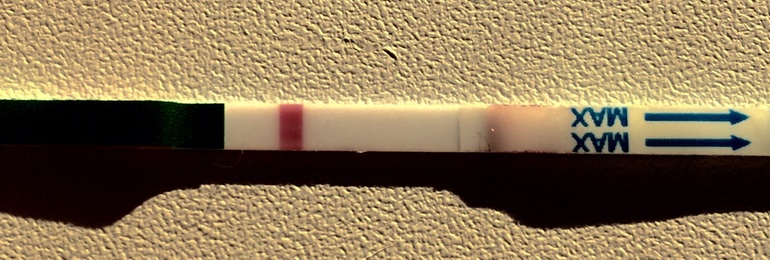

Вот сейчас вообще вижу 2 тоненьких полоски, как очертания жирной одной. Я одна такая ?или глючит?

А может это колективная галлюцинации:-D Когда следующий тест? Я в предвкушении

А вот и узнаем скоро, а тест какой? У меня тест через 10 часов среагентил:-) так что жду твоих и моих полосок

Вот я ни разу не видела реагенты, хотя беру тоже дешевые,тут в Но можно разориться на тестах:-) Еще тут на бб куча историй про 8 дпо с полоской, и самые дешевые тесты самые первые показывают. Поройтесь в копилке тестов.